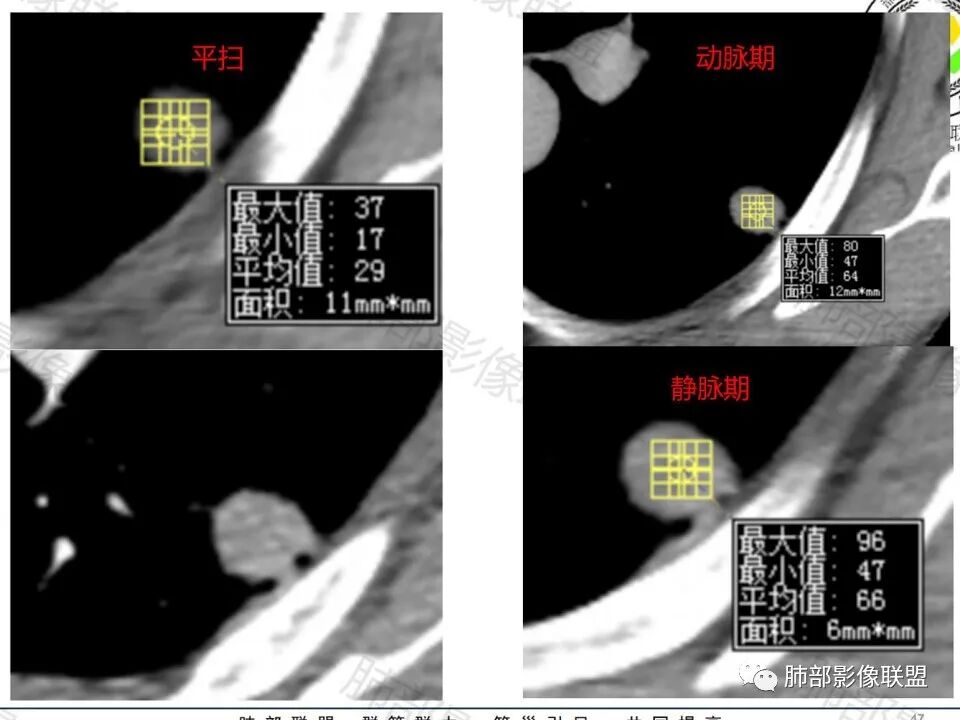

影像:轻微肺气肿,可能抽烟;旁边有个卫星灶4-5个,厚层无血管弯,薄层叶间裂轻度增厚,有囊腔,内侧有一个微血管,弯,另有两个微血管直,膨隆,增强血管不弯,糊墙,好像边界有些模糊,17-47-47,冠位轻度叶间裂弯。

这枚结节的纵隔窗在没有调节窗位的情况下,已经很密实了,说明这个结节里面是软组织的成分,这与普通炎性结节(隐球菌等)的密度还是有区别的,很多年前就有人提出,纵隔窗显示越大,恶性可能越大;

结节周围有磨玻璃影,边界似清不清的,但是总体不如炎性晕征那么模糊;

增强的程度很难讲,但是不均匀强化是可以确定的;

有收缩力,但是很轻,按照常理,实性结节因为有占位效应,不太会有收缩力,但是叶间胸膜有凹陷。所以讲,这个结节还是开了放心。